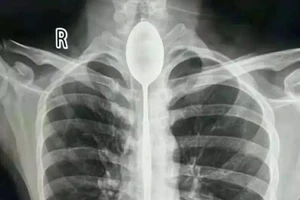

Mắc kẹt thìa dài 20 cm trong thực quản suốt 1 năm